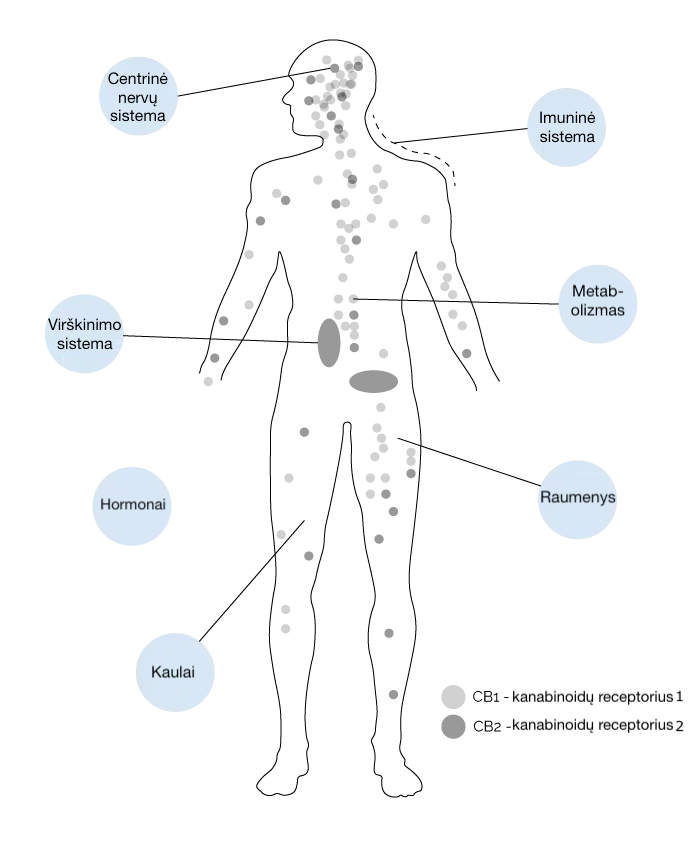

Endokanabinoidų sistema užtikrina organizmo fiziologinę pusiausvyrą.Endokanabinoidų sistema (ECS)

Endokanabinoidų sistema (ECS) aptinkama visuose žinduoliuose. Ji yra būtina vidinei organizmo komunikacijai. Būtent dėl ECS mes nesame tik ląstelių visuma, o tiksliai funkcionuojantis žmogaus organizmas.

Ši unikali sistema dalyvauja daugelyje svarbių organizmo procesų – ląstelių dalijimesi, taip pat smegenų, nervų ir imuninės sistemos veikloje. Ji atlieka svarbų vaidmenį bendroje sveikatoje ir organizmo gebėjime susidoroti su įvairiais su sveikata susijusiais sutrikimais.

ECS sudaro kanabinoidų receptoriai, endokanabinoidai ir fermentai. Svarbiausi iki šiol ištirti endokanabinoidai, kuriuos organizmas gamina pats, yra anandamidas (ANA) ir 2-arachidonoilglicerolis (2-AG) – jie padeda reguliuoti ir palaikyti pusiausvyrą daugelyje organizmo procesų.

Kanabinoidų receptoriai

Kanabinoidų receptoriai yra žmogaus organizmo ląstelių paviršiuje ir „priima“ signalus iš išorinės ląstelės aplinkos. Jie perduoda informaciją apie pokyčius ląstelės viduje ir inicijuoja atitinkamas ląstelių reakcijas.

Yra žinomi du pagrindiniai kanabinoidų receptoriai — CB1 ir CB2. Jie nėra vieninteliai, tačiau buvo pirmieji atrasti ir iki šiol yra plačiausiai ištirti.

CB1 ir CB2 receptoriai yra pagrindiniai endokanabinoidų sistemos (ECS) elementai.

CB1 receptoriai daugiausia randami centrinėje nervų sistemoje, įskaitant smegenų neuronus, o CB2 receptoriaidažniausiai aptinkami už nervų sistemos ribų, pavyzdžiui, imuninės sistemos ląstelėse.